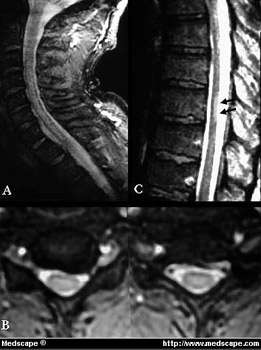

Figure 2. MRI showing spinal cord DCS (cervical and dorsal tract). Reprinted from the Journal of Magnetic Resonance Materials in Physics, Biology and Medicine.

La risonanza magnetica nucleare (MRI) mostra malattia da decompressione del tratto cervicale e dorsale del midollo spinale

Figure 3. Spinal cord DCS (cervical tract). Reprinted from the Journal of Magnetic Resonance Materials in Physics, Biology and Medicine. Malattia da decompressione del tratto cervicale del midollo spinale